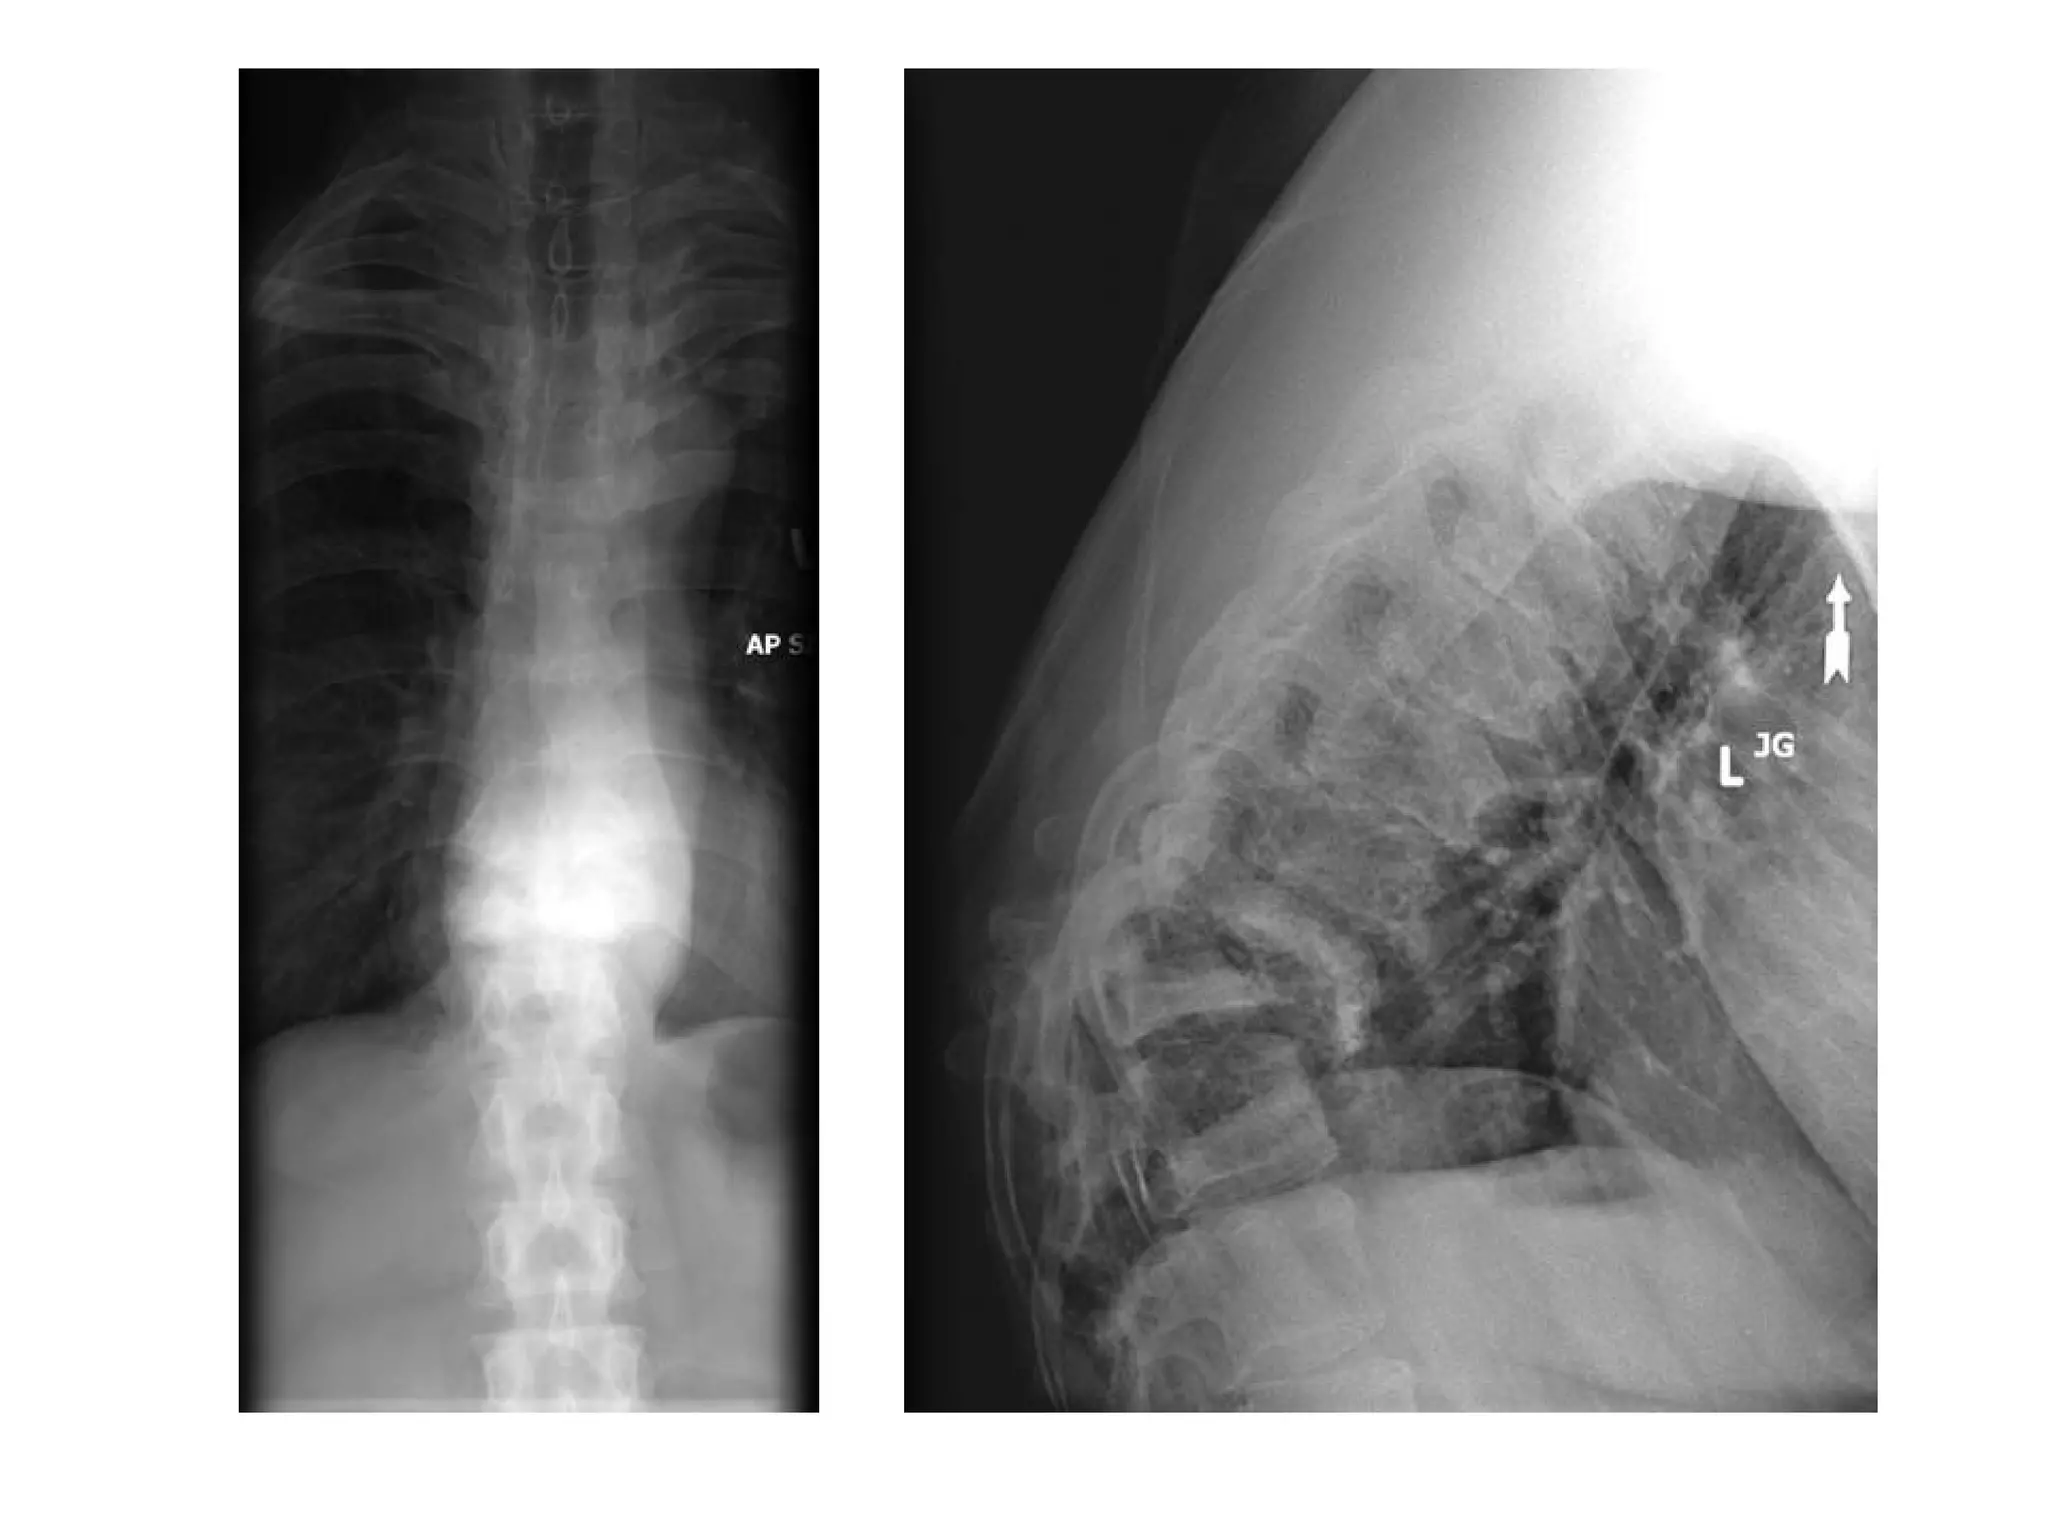

Spondylosis deformans , lateral radiograph of the lumbar spine reveals osteophyte

formation (arrows) , these initially extend in a horizontal direction and then in a

vertical one , severe apophyseal joint osteoarthritis is also present